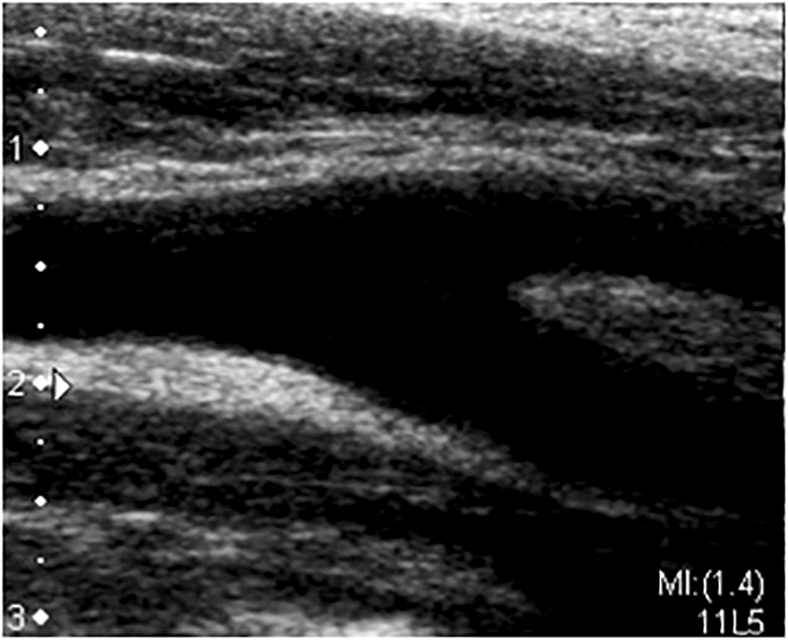

超音波(人の耳には聞こえない高い周波数の音波)を体の表面にあて、体内の臓器を画像化し、臓器の形態や血流情報をリアルタイムに観察する検査です。

頸動脈の血管壁の厚さ(IMT)、プラーク(動脈硬化に伴う血管壁の隆起病変)による血管内の狭窄や閉塞の有無、血流の状態などを観察します。

頸動脈の血管壁の厚さは、全身の動脈硬化の指標となります。